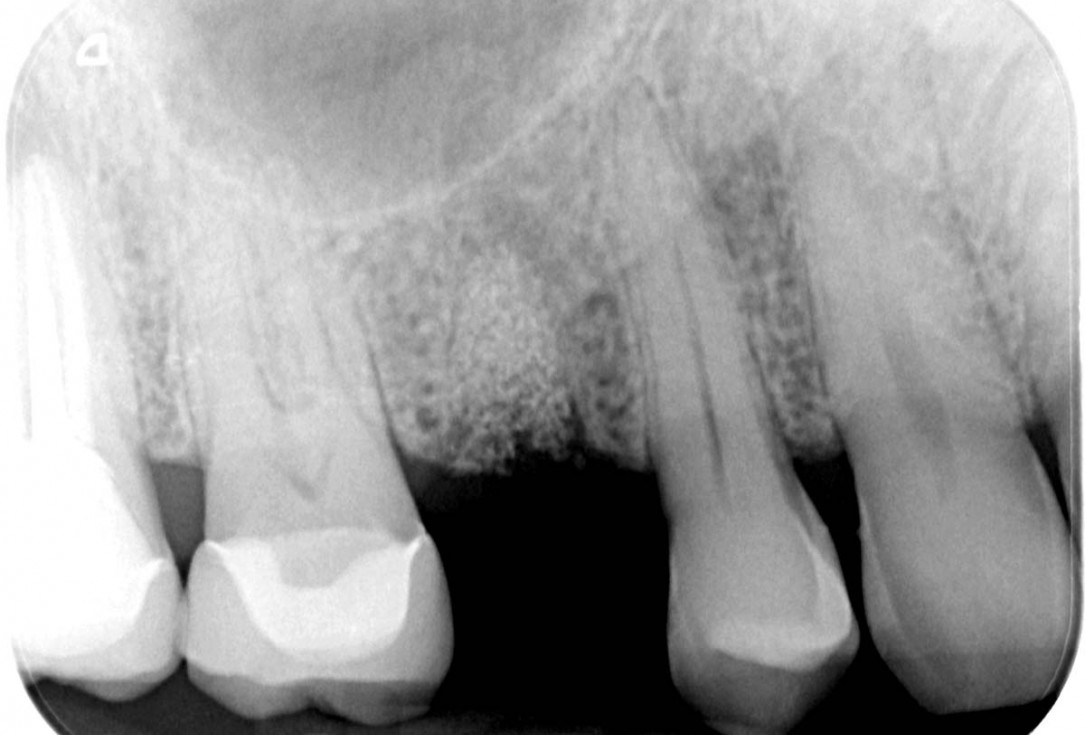

01/06 - Extraction socket grafted with cerabone.Socket preservation with cerabone® - Dr. P. Kämmerer

Extraction socket grafted with cerabone.